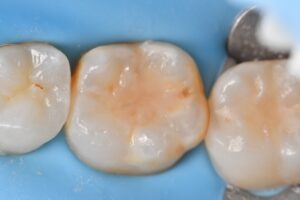

A narrow contact area can often suffer from significant lateral impaction of food debris. With the presence of hypomineralization, this is a carious lesion that can rapidly seed and progress. Every effort was made to broaden the contact area on the distal of this molar to mitigate the above concerns.

#KerrSimplishade #GarrisonCompositight